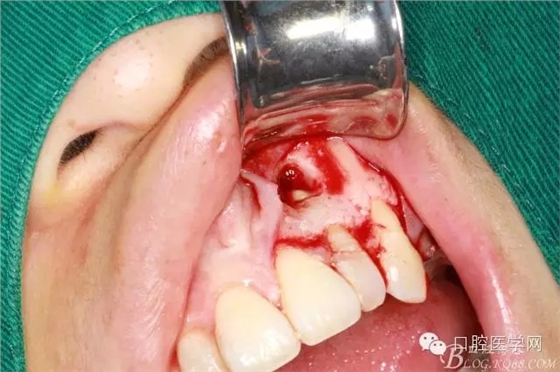

刮凈囊腫

繼續(xù)去骨暴露牙根

牙根露出3mm左右因?yàn)楦虚L度

沖洗干凈開窗處

根切后可見開窗處清理干凈

刮出囊腫及牙根2.5MM

填明膠海棉(建議植骨和應(yīng)用生物膜)患者不同意因費(fèi)用較高

復(fù)位縫合

填塞牙周塞治劑